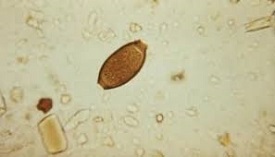

10 - Scientists link new virus to kala-azar

A group of scientists from West Bengal and Uttar Pradesh has made a point that an unknown virus, called Leptomonas seymouri, may be responsible for the persistence of kala-azar or visceral leishmaniasis. Historically, the parasite Leishmania donovani is believed to be responsible for the disease.

The researchers found the L seymouri and a virus called Lepsey NLV1 within it in 20 of 22 biological samples of patients who had a residual L donovani infection.